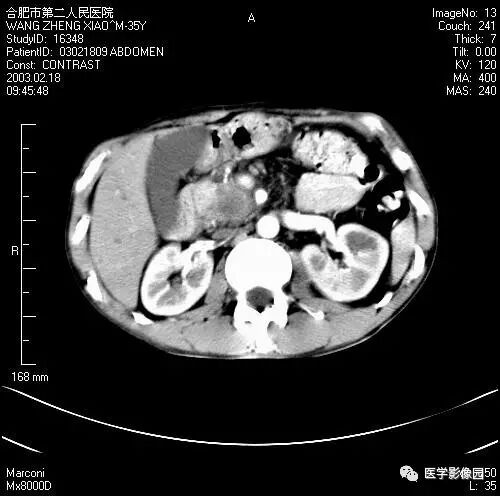

图6-4-12胰腺癌

增强扫描胰腺钩突失去正常平直的三角形,

呈不规则分叶状